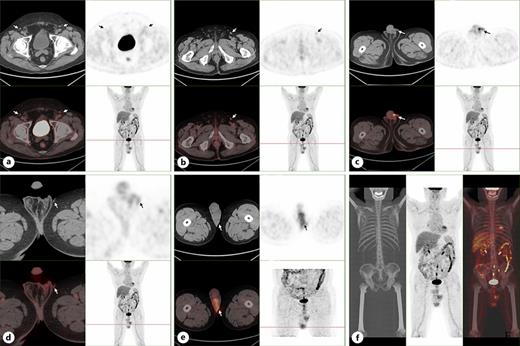

A 74-year-old male patient was admitted to our department due to experiencing patchy erythema and pruritus in the perineal area for over 5 years and the lesions progressively expanding with skin ulceration over the past 3 months. Five years ago, the patient initially noticed the patchy erythema on the scrota skin, which was covered with a small amount of white scales and accompanied by pruritus. The patient initially used acyclovir ointment to treat it by himself. After the pruritus symptoms relieved, the patient did not seek further medical care. However, 3 months ago, the patient observed that the lesions of scrota skin had gradually expanded to the pubic mound and penis, so he was admitted to our hospital for treatment. The patient had a medical history of hypertension for more than 14 years and diabetes for over 3 years. Upon physical examination, no abnormalities were detected in all systematic examinations and no enlargement of the lymph nodes was found in the bilateral inguinal region. Flake erythema of about 12.5 cm × 10.0 cm could be seen in the scrotum, penis, and pubic mound, with a few white scales overlying it. Skin ulceration and dark red blood scabs could be observed in the lesion. There were clear boundaries between the lesion and surrounding tissue (Fig. 1). There were no obvious abnormalities in blood routine, urine routine, liver and kidney function, and other laboratory examination tests. PET/CT results showed that the skin of bilateral scrotum was slightly thickened with increased metabolism, which was consistent with the appearance of malignant tumor, and the density and metabolism of the left testis were increased, which were considered as tumor invasion (Fig. 2). In histopathological examination, many scattered vacuolated Paget cells were observed in the epidermal layer, which had large cell bodies, abundant and light-stained cytoplasm, large and dark-stained nuclei. Besides, abnormal mitotic images were observed in Paget cells (Fig. 3). Immunohistochemical results showed GCDFP-15(focal +), CK7(+), CK20(+), EMA(+), MUC5AC(+), CEA(+), GATA3(+), CK5/6(−), P40(−), P63(−), Ber-EP4(−), KI-67(+30%), P53(+5%), CD56(−), Syn(−), AR(+) (Fig. 4). The pathological diagnosis was Paget’s disease of the scrotum and penis. Under general anesthesia, a wide local excision (WLE) of the lesion, bilateral orchiectomy, and adnexectomy were performed on the patient. The 2 cm outside the skin lesion was used as the initial surgical margin, and free skin flap transplantation was used to repair the surgical wound. The patient recovered well and was discharged 1 week after surgery.

a Metabolic status of bilateral inguinal lymph nodes. b The metabolism of the left inguinal lymph node is increased. c, d The scrotal skin on both sides was thickened and the metabolism was increased, especially on the left side. e The density and metabolism of left testis were increased, considering tumor invasion. f Metabolic status of whole body tissues. a-f PET/CT results showed that the skin of bilateral scrotum was slightly thickened with increased metabolism, and the density and metabolism of the left testis were increased, which were considered as tumor invasion.